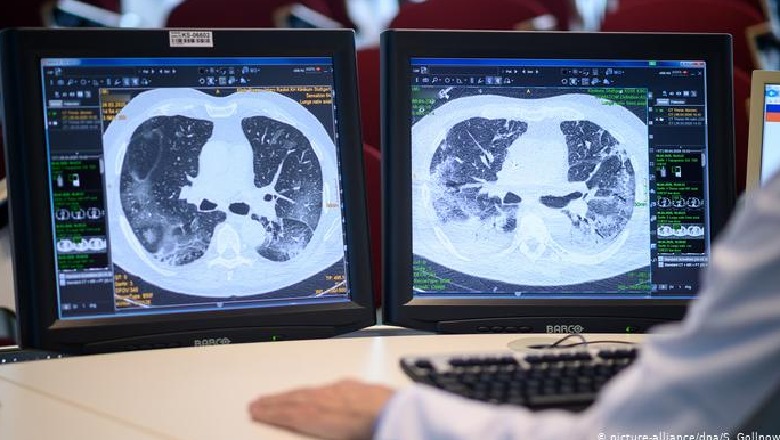

Mauro Jacket, profesor i Shkencave Kardiovaskulare në Kolegjin Mbretërorë të Londrës tha për ‘The Guardian’ se te pacientët në gjendje të rëndë dhe sidomos te ata që nuk i kanë mbijetuar infeksionit nga koronavirusi, mushkria si organ nuk ekziston më.

“Arkitektura e mushkrive te ata që qëndrojnë rreth 40 ditë në terapi intensive, nuk ka asgjë të përbashkët me ndërtimin e mushkrive që njohim ne”.

Duke ekspozuar studimin e tij, të kryer duke ekzaminuar disa qindra autopsi të pacientëve të vdekur në Itali pasi kishin kaluar 40 ditë në repartet e Terapisë Intensive, Jacket tha në Parlamentin anglez, se

“Ajo që kam gjetur është shumë e pazakontë. Plotësisht e ndryshme nga pneumonia e shkatuar gripi apo SARS” dhe theksoi se “Te këta pacientë trompozat e shkaktuara ishin masive dhe arkitektura e mushkrive ishte totalisht e shpërbëre. Në shumë raste e kishte patur të pamundur të dallonte ekzistencën e mushkrisë”.